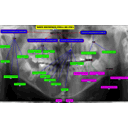

Recursos para TUMORES ODONTOGENICO maestria F

TUMORES ODONTOGENICO maestria F.cmap